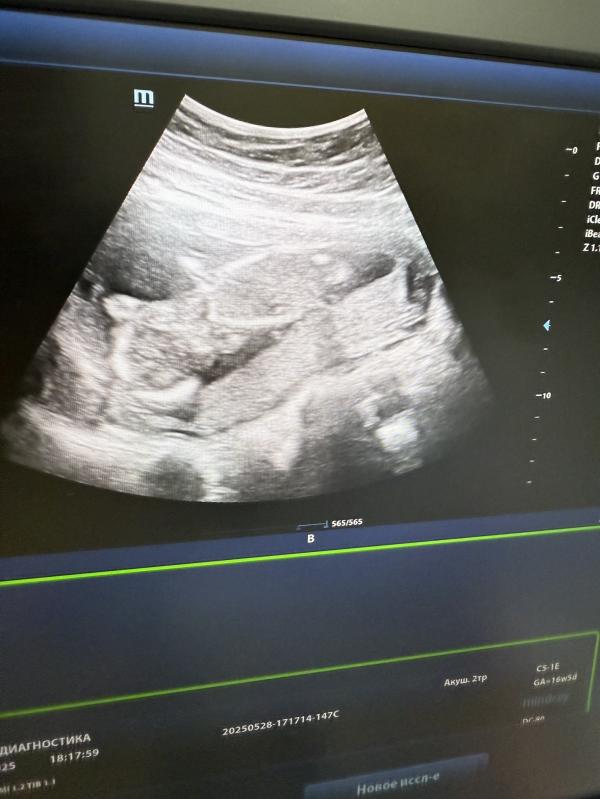

post image

Поделитесь фоточками своего узи срок примерно мой 😅

Была сегодня на узи , так необычно лежит, вниз головой. С дочкой обычное положение было 🫣

Согласна

Очень непонятное узи 😅

Мне сегодня сказали что вроде как девочка но это не точно